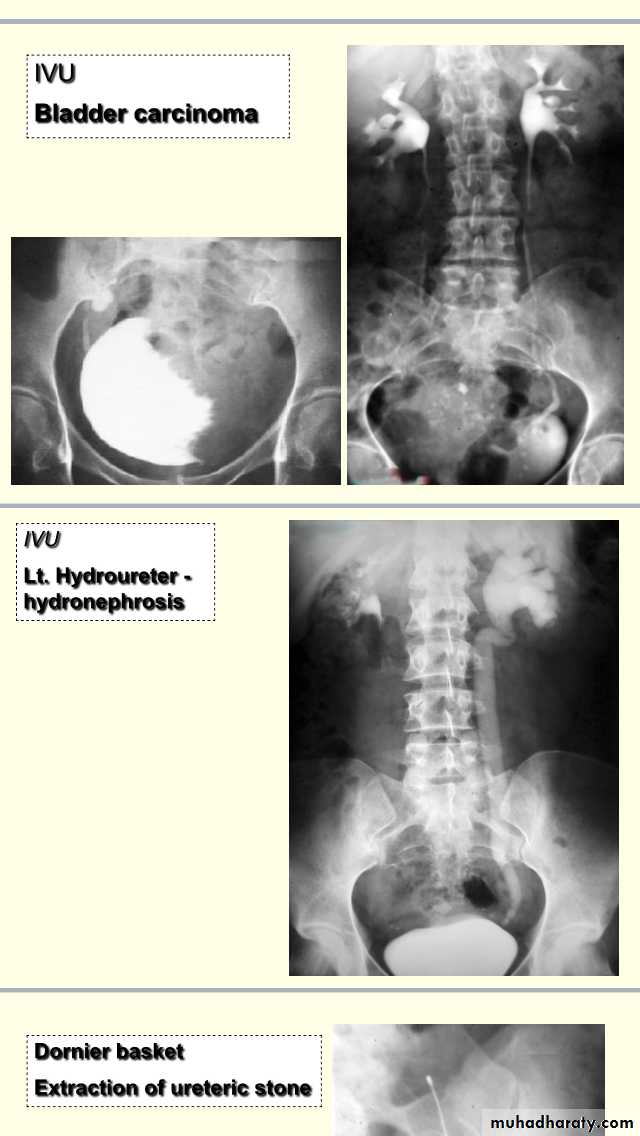

Uroradiology & Slides 1